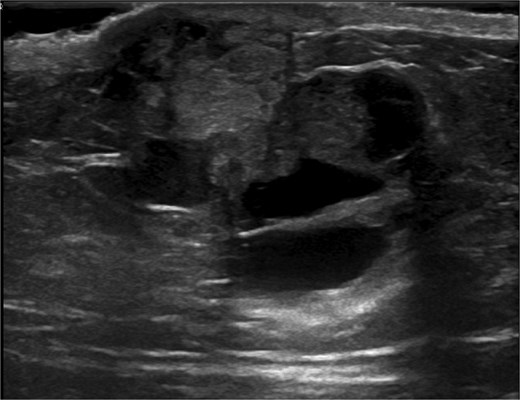

Ultrasound-guided core needle biopsy of the mass showed dissociated fragments of cribriform-like and papillary-like carcinoma (Figs 3 and 4).

Ultrasound of retroareolar area of palpable concern – second view.